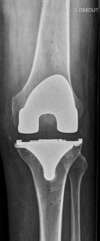

prothèse totale de genou

prothèse totale de genou : vue schématique de profil des 3 composants posés (pièces fémorale, tibiale et patellaire)

Même patient que précédemment après chirurgie assistée par ordinateur (Navigation) : prothèse totale de genou